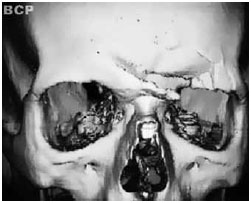

Figura 2 - Tomografia computadorizada com reconstrução tridimensional.